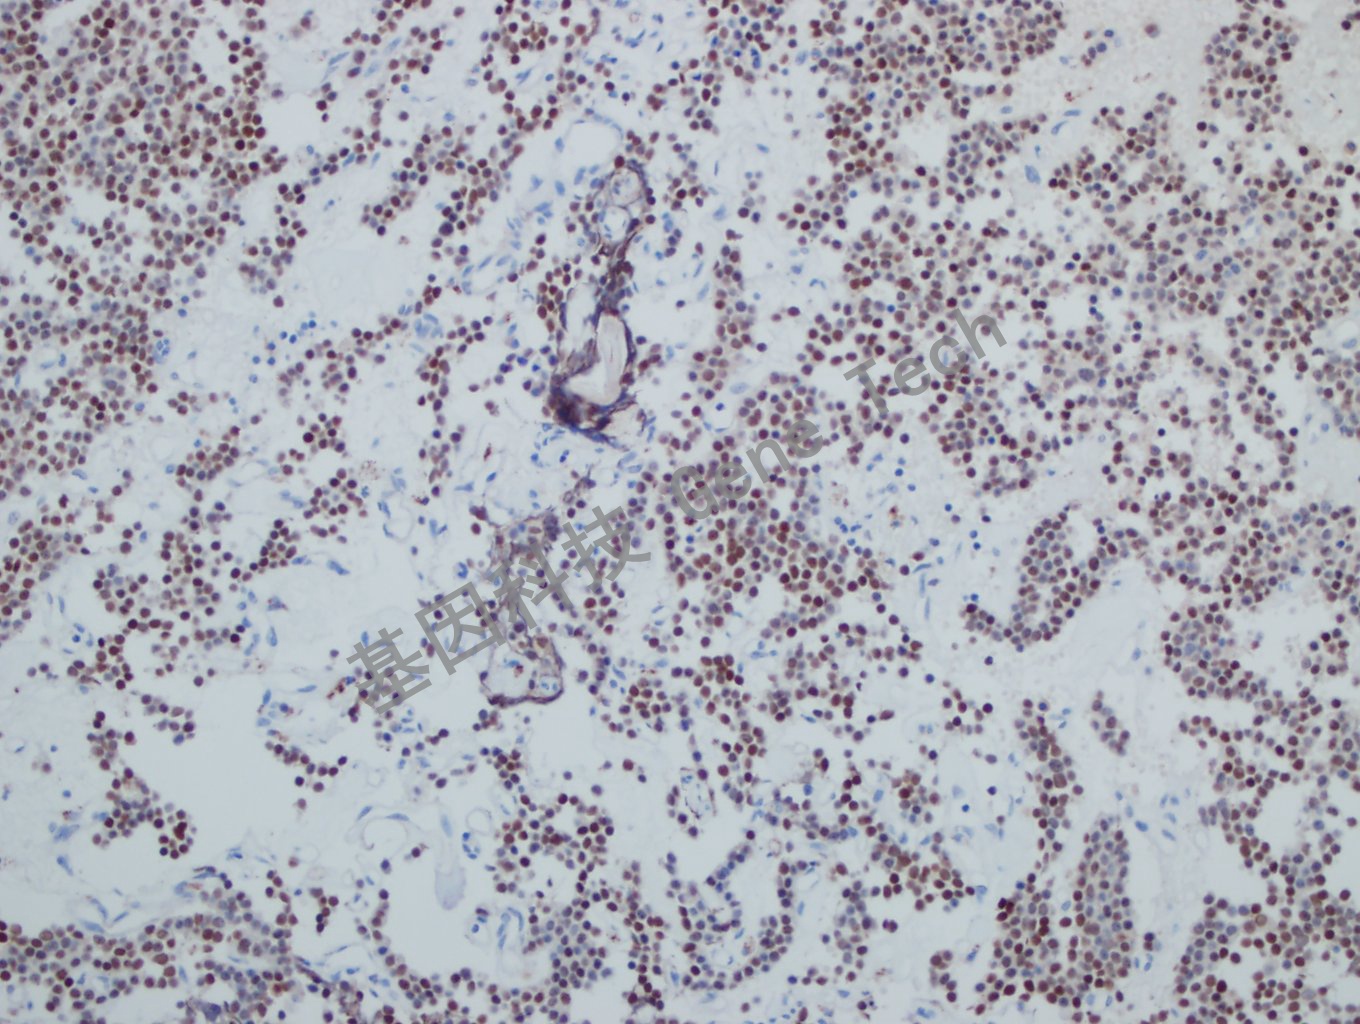

垂体腺瘤石蜡切片,用 SF-1(GT2317)染色,细胞核阳性,DAB显色。